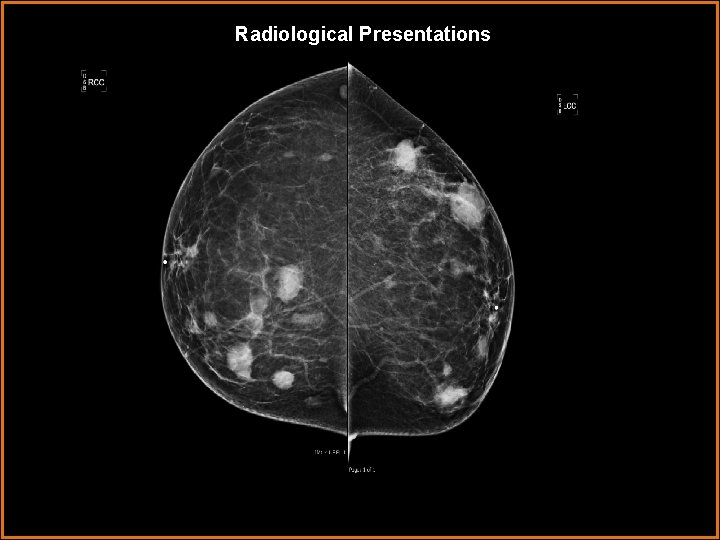

Case History 51 year old female presenting for a routine screening mammogram. Previous mammogram (2 years before) was normal.

Radiological Presentations

Findings and Differentials Findings: The mammogram demonstrates multiple masses within the breasts, bilaterally. Differentials: • Primary breast cancer with metastatic disease. • Multifocal breast cancer versus synchronous breast cancer. • Cutaneous lymphoma. • Multiple cysts • Multiple fibroadenoma